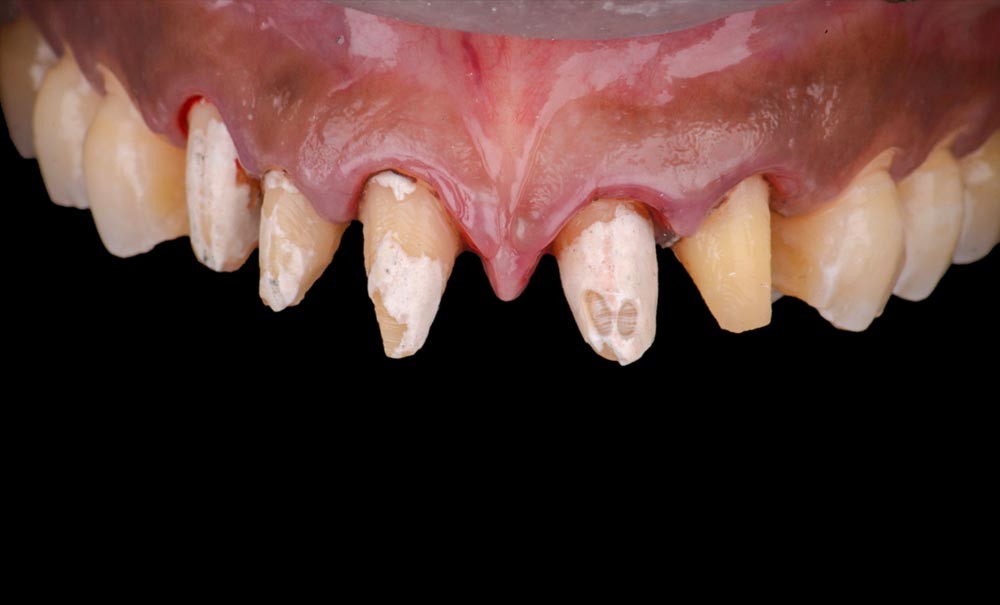

L’analyse esthétique montre notamment (fig. 1 et 2) :

- un ratio des incisives centrales de 78 % ;

- un diastème inter-incisif de 1 mm considéré comme disgracieux par la patiente ;

- un décalage des collets de 12 et 22 ;

- un défaut de teinte des facettes existantes sur 12 et 22.

Afin de valider le résultat esthétique de la correction des diastèmes et du décalage des collets, un mock-up de motivation est réalisé en technique directe (fig. 3).